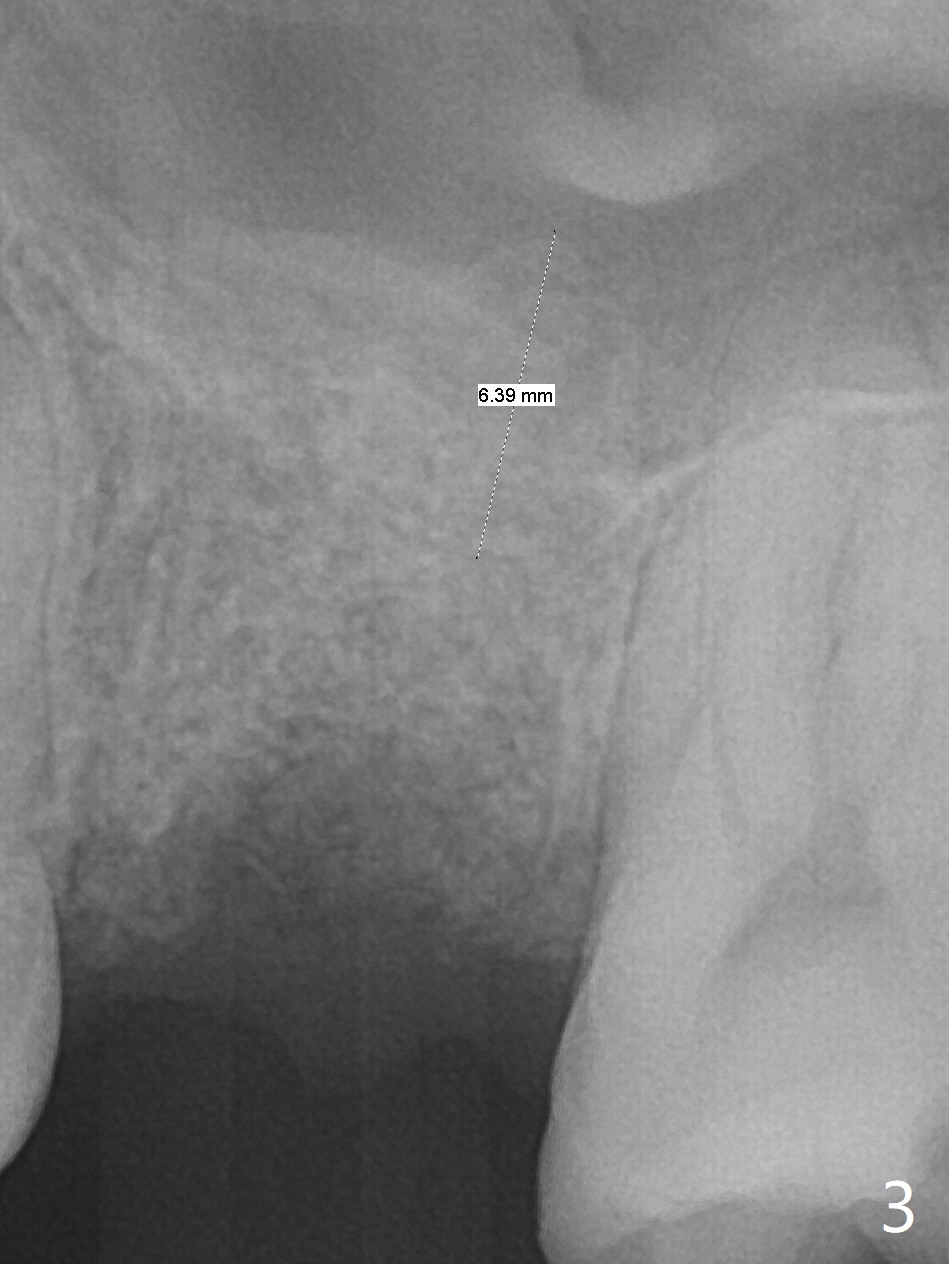

A 38-year-old woman requests extraction of the tooth #14 with mesiobuccal fistula (Fig.1). After extraction, the buccal plate is found to be defective. Bone graft enters the apex of the palatal root (Fig.2 red dashed line) so that the bone height increases by 6 mm (Fig.3). Following placement of collagen plug and suturing, acrylic dressing is applied to the undercuts of the neighboring teeth for retention.